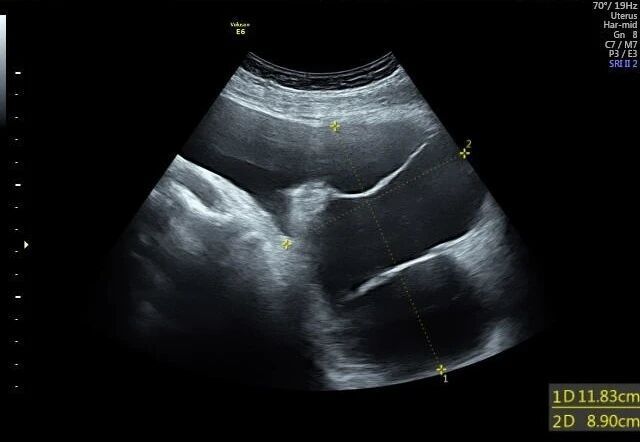

1. 超声检查:首选且最常用的检查。B超下可见盆腔内囊性无回声区,边界多不清晰,形态不规则,囊壁薄而模糊,内部无血流信号,结合患者有手术史或盆腔炎病史,可初步诊断。

图片